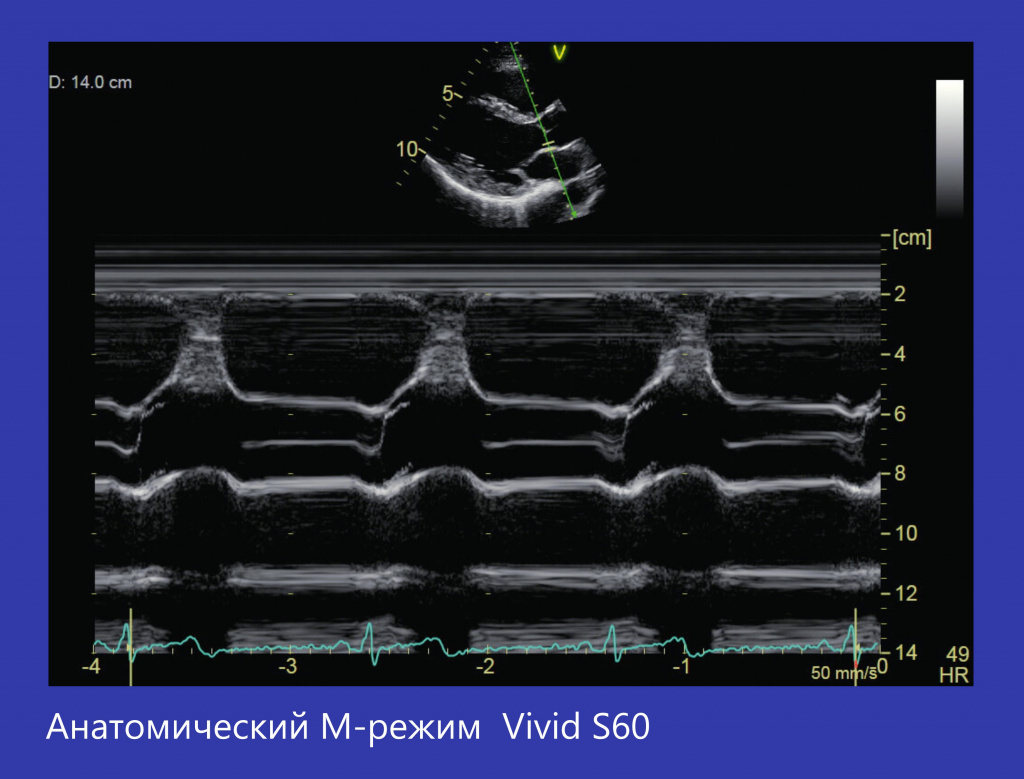

AM-mode |

Анатомический М-режим |

C-curved A-anatomical M-Mode |

М-режим (Анатомический и криволинейный) |